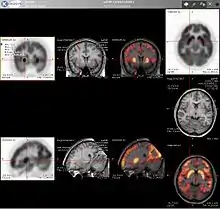

PET imaging with 18F-FDG takes advantage of the fact that the brain is normally a rapid user of glucose. Standard 18F-FDG PET of the brain measures regional glucose use and can be used in neuropathological diagnosis.

- Brain pathologies such as Alzheimer's disease greatly decrease brain metabolism of both glucose and oxygen in tandem. Therefore 18F-FDG PET of the brain may also be used to successfully differentiate Alzheimer's disease from other dementing processes, and also to make early diagnoses of Alzheimer's disease. The advantage of 18F-FDG PET for these uses is its much wider availability. Some radioactive tracers used for Alzheimer's are florbetapir 18F, flutemetamol F18, PiB and florbetaben 18F, which are all used to detect amyloid-beta plaques (a potential biomarker for Alzheimer's) in the brain.

- PET imaging with FDG can also be used for localization of seizure focus: A seizure focus will appear as hypometabolic during an interictal scan. Several radiotracers (i.e. radioligands) have been developed for PET that are ligands for specific neuroreceptor subtypes such as [11C] raclopride, [18F] fallypride and [18F] desmethoxyfallypride for dopamine D2/D3 receptors, [11C] McN 5652 and [11C] DASB for serotonin transporters, [18F] Mefway for serotonin 5HT1A receptors, [18F] Nifene for nicotinic acetylcholine receptors or enzyme substrates (e.g. 6-FDOPA for the AADC enzyme). These agents permit the visualization of neuroreceptor pools in the context of a plurality of neuropsychiatric and neurologic illnesses.

The development of a number of novel probes for noninvasive, in vivo PET imaging of neuroaggregate in human brain has brought amyloid imaging to the doorstep of clinical use. The earliest amyloid imaging probes included 2-(1-{6-[(2-[18F]fluoroethyl)(methyl)amino]-2-naphthyl}ethylidene)malononitrile ([18F]FDDNP)[15] developed at the University of California, Los Angeles and N-methyl-[11C]2-(4'-methylaminophenyl)-6-hydroxybenzothiazole[16] (termed Pittsburgh compound B) developed at the University of Pittsburgh. These amyloid imaging probes permit the visualization of amyloid plaques in the brains of Alzheimer's patients and could assist clinicians in making a positive clinical diagnosis of AD pre-mortem and aid in the development of novel anti-amyloid therapies. [11C]PMP (N-[11C]methylpiperidin-4-yl propionate) is a novel radiopharmaceutical used in PET imaging to determine the activity of the acetylcholinergic neurotransmitter system by acting as a substrate for acetylcholinesterase. Post-mortem examination of AD patients have shown decreased levels of acetylcholinesterase. [11C]PMP is used to map the acetylcholinesterase activity in the brain, which could allow for pre-mortem diagnoses of AD and help to monitor AD treatments.[17] Avid Radiopharmaceuticals has developed and commercialized a compound called florbetapir that uses the longer-lasting radionuclide fluorine-18 to detect amyloid plaques using PET scans.[18]